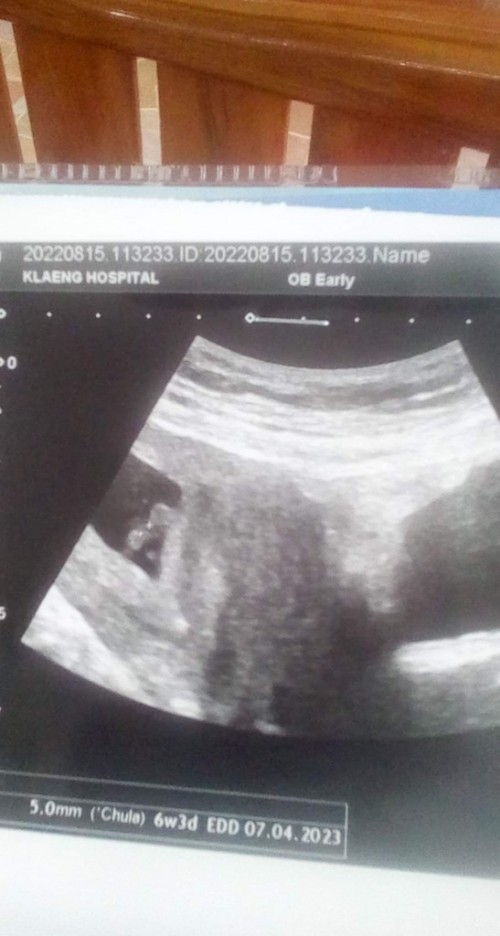

อัลตร้าซาวด์ตอน6วีค1วัน

ซาวน์ ตอน 6W5D เจอถุงตั้งครรภ์ ถุงไข่แดง ตัวน้อง และสัญญาณชีพ ครบค่ะ สู้ๆนะคะ แต่ละคนอาจจะไม่เหมือนกัน ไม่ต้องกังวลนะคะ รออีกสัก 1-2 สัปดาห์ก็น่าจะเห็นแล้วจ้า